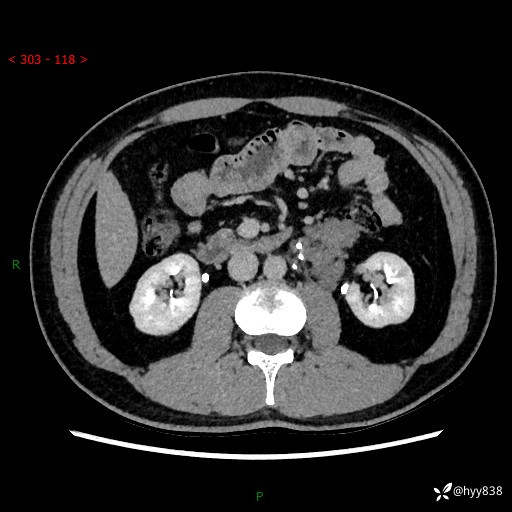

现病史:患者3月余前检查发现左侧腹膜后占位,大小约3.7*4.9cm,平素无腰疼,无肉眼血尿,无尿频尿急等不适,当时未特殊处理,在门诊复查CT提示左侧腹膜后占位,门诊拟“左侧腹膜后占位”收入院。 起病以来,患者精神佳,饮食、睡眠良好,大小便正常,体力体重无明显变化。

腹膜后CT平扫+增强